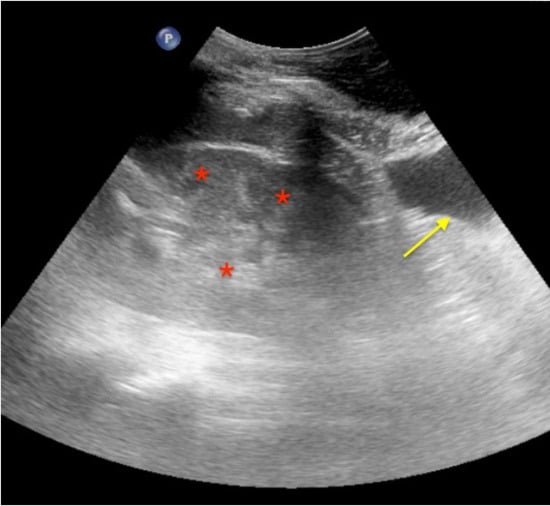

Real Images

Pneumothorax